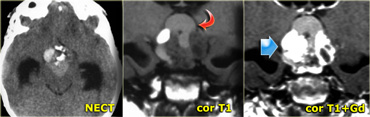

Schwannoma in CPA-region with typical features of an extraaxial tumor (T2WI) Schwannoma in CPA-region with typical features of an extraaxial tumor (T2WI)

The T2W-images show a schwannoma located in the cerebellopontine angle (CPA).

This case nicely demonstrates the typical signs of an extra-axial tumor.

There is a CSF cleft (yellow arrow).

The subarachnoid vessels that run on the surface of the brain are displaced by the lesion (blue arrow).

There is gray matter between the lesion and the white matter (curved red arrow).

The subarachnoid space is widened because growth of an extra-axial lesion tends to push away the brain.

All these signs indicate that this is a typical extra-axial tumor.

In the region of the CPA 90% of the extra-axial tumors are schwannomas.

Coronal enhanced T1WI. Meningioma with dural tail, hyperostosis of adjacent bone and homogeneous enhancement Coronal enhanced T1WI. Meningioma with dural tail, hyperostosis of adjacent bone and homogeneous enhancement

Another sign of an extra-axial origin is a broad dural base or a dural tail of enhancement as is typically seen in meningiomas.

This may also occur in other extra-axial tumors, but it is less common.

Another sign of an extra-axial origin are bony changes.

Bony changes are seen in bone tumors like chordomas, chondrosarcomas and metastases.

They can also be secondary, as is seen in meningiomas and other tumors.

On the left an example of a meningioma with a broad dural base and a dural tail of enhancement.

There is hyperostosis in the adjacent bone and the lesion enhances homogeneously.

Extra-axial tumors are not derived from brain tissue and do not have a blood-brain-barrier, so most of them enhance homogeneously.